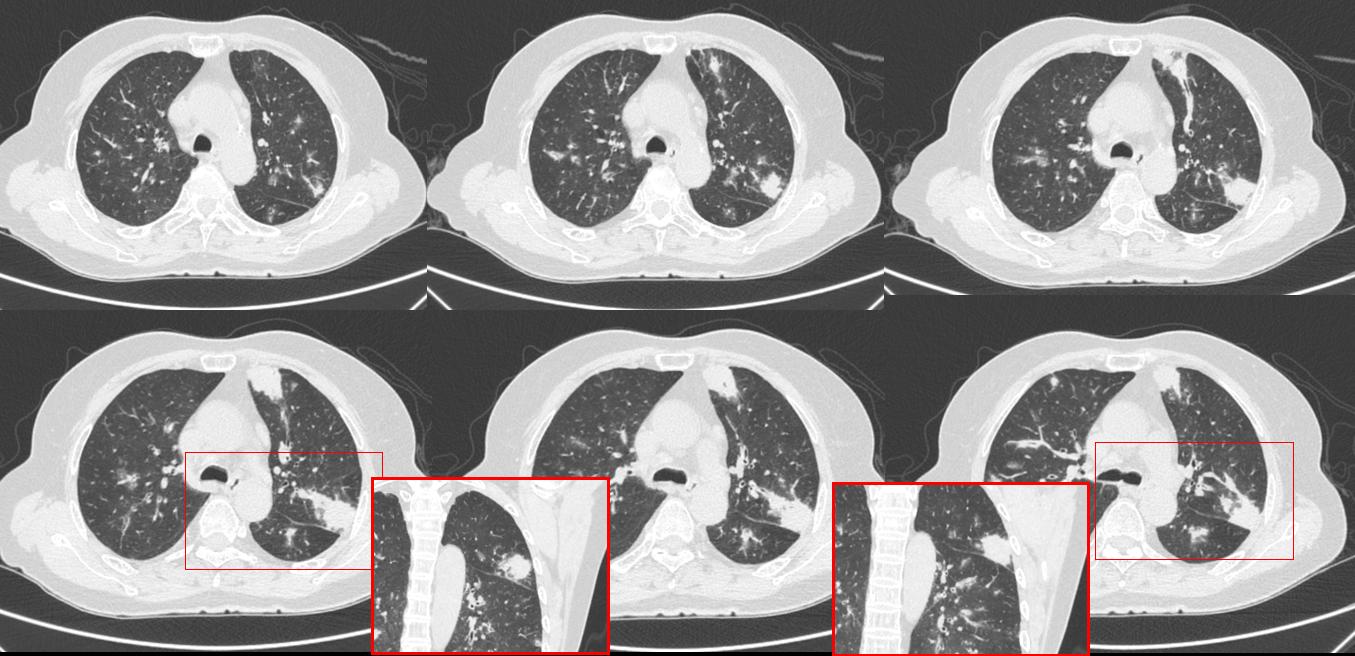

图像:

影像描述:多发结节状、条片状密度增高灶,边界欠清,多发腺样小结节改变。

影像诊断:考虑特殊感染CT表现。

病理:嗜酸性肉芽肿性多血管炎

B:影像还说啥了,结节样改变,唯一特异点的就是沿着血管支气管。可以查查血管炎的标志物。所以说我老师说得好,肺的病都一样,只要知道不是肿瘤就好了,都基本看临床,话也说回来,看病太不容易了,查血差那么多,还不知道是个啥,也没个头啊。查这些东西又费钱,还要排队,本来就生病着急,要我我也烦。

③:影像特点三多:多发,多样(空洞样、实性结节样多见,也可呈片状、楔形),多变(部位、大小、形态可随着治疗发生变化)。